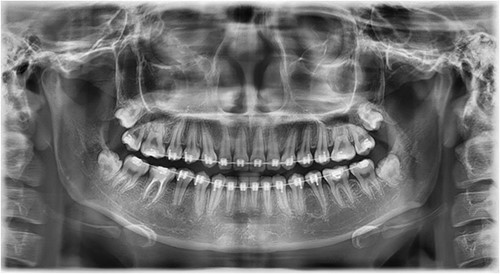

In this context, a buccal approach using a Neumann full-thickness flap was preferred (Fig. 4). When a buccal approach is planned, then the location of the mental nerve must be identified to avoid any post-operative sensory problems. The most challenging part is to exercise extreme caution during Ostectomy to avoid damage to the adjacent tooth roots.